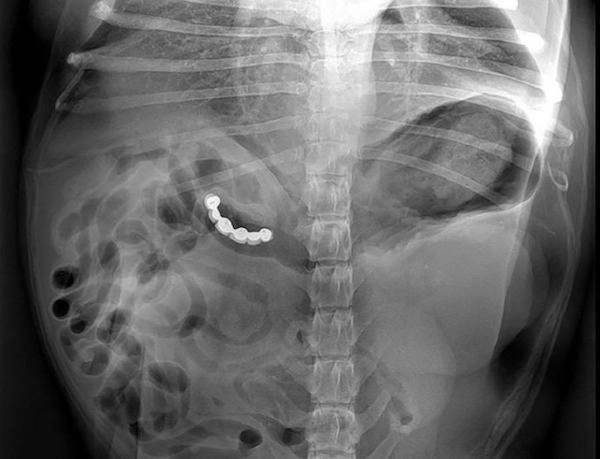

/ 15Sztuczna szczęka

Pożarł zęby z wrażenia.